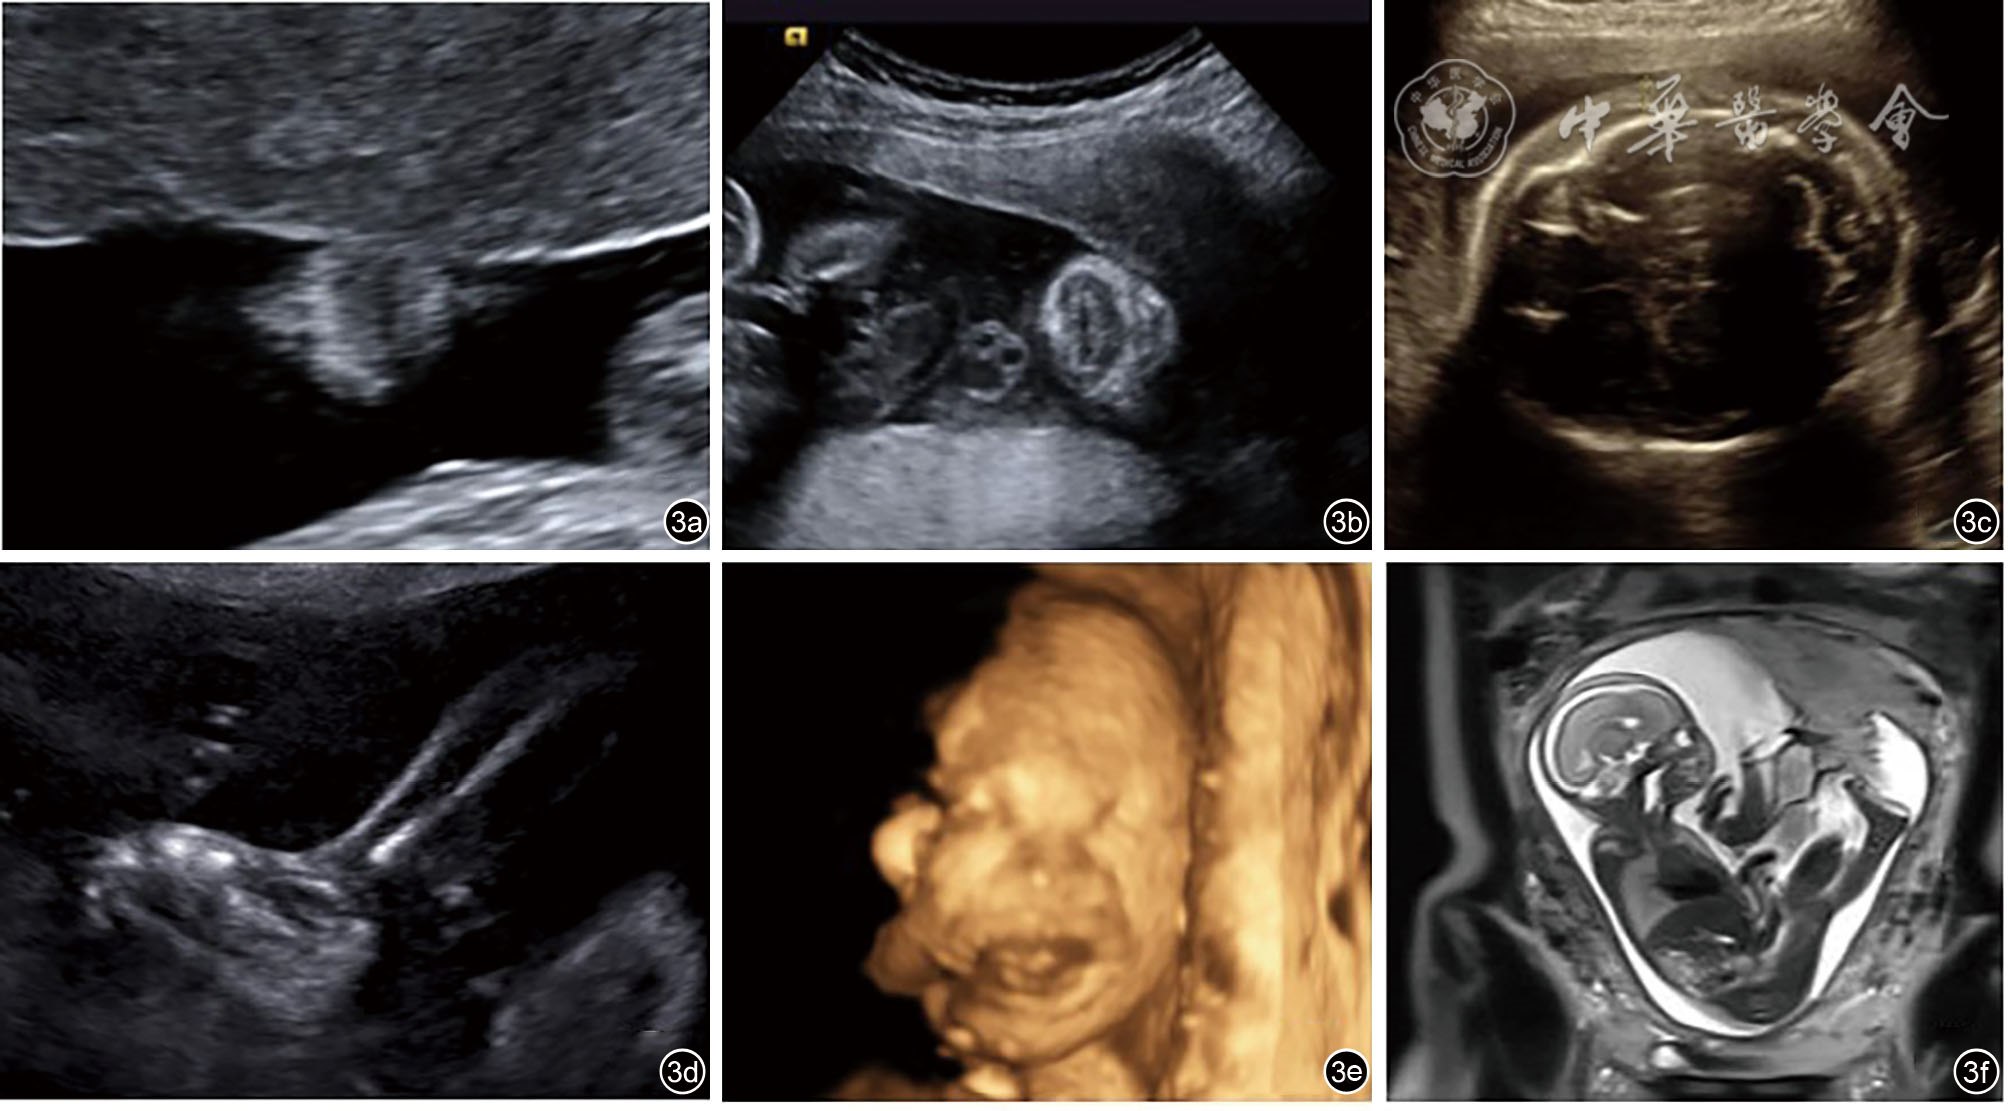

图1 先天性丑角鱼鳞病(病例1)超声图像。图a示胎儿头皮明显增厚;图b示胎儿双眼球前方均见一向前突起的团状稍高回声;图c示胎儿嘴唇增厚外翻;图d示胎儿胸腹部及背部皮肤增厚回声增强,多处回声连续性中断;图e示胎儿双手呈握拳状;图f示双足皮肤增厚